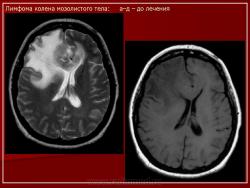

ГМ. Онк. Лимфомы головного мозга. Набор изображений. +

Лимфомы головного мозга.